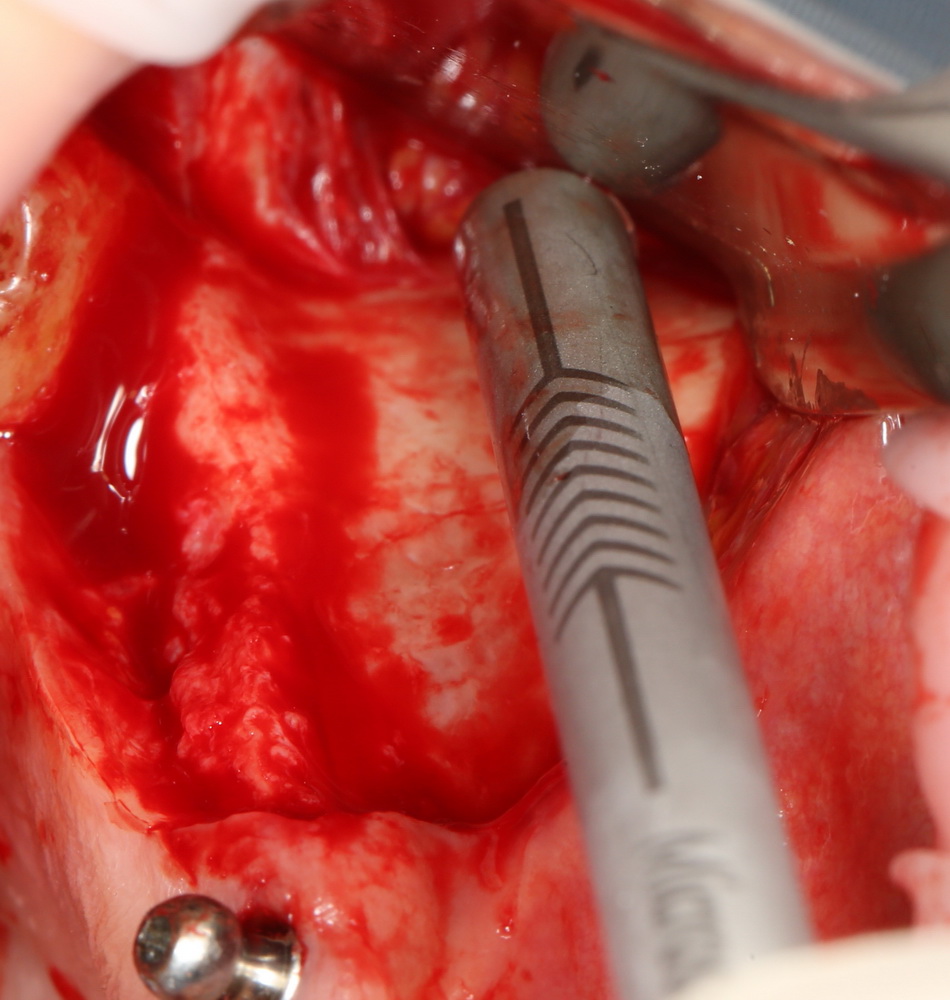

Что же касается нерезорбируемых мембран… Было дело, работал с Gore-Tex (дорого, очень дорого), титановыми сетками (заколебался потом доставать) и тефлоновыми Cytoplast:

результат:

или

с трудом выковыриваем сетку и ищем имплантат:

чтобы поставить формирователь: